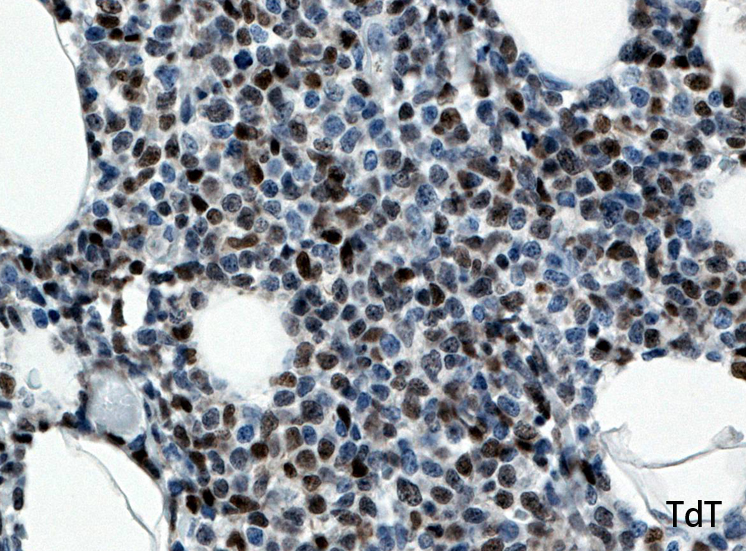

罹患リンパ節の基本構造は消失し腫瘍細胞のびまん性増殖で置換されている。非腫瘍性の小リンパ球(CD3+, CD4/8+)が濾胞様に散在して残る(Fig.01)。不整型または類円形の明るい核をもつmedium-sizeのリンパ球様細胞が密に増殖している。細胞質は乏しい(Fig.02)。CD68陽性macrophageが多く混在する部分が認められた。

Fig03, Fig04は腫瘍細胞の拡大像。大型異型細胞の出現が認められる。腫瘍細胞はCD4+, CD56+, CD123+